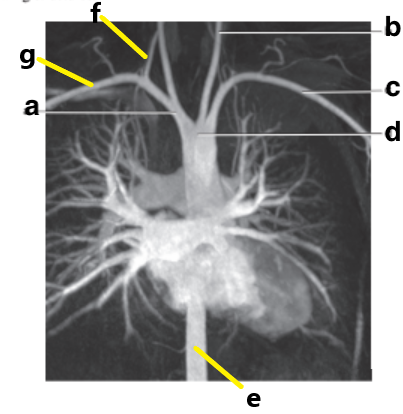

What is letter b ?

Esophagus

Which letter is the Pulmonary trunk ?

d

Which letter is the Descending aorta ?

f

Which letter is the superior vena cava ?

Which letter is the Left common carotid ?

b

Which letter is the left subclavian artery ?

Which letter is the Right common carotid artery ?

What is letter a ?

Brachiocephalic trunk

Which letter is the ascending aorta ?

Ascending aorta

Which letter is the Right vertebral artery ?

c

Which letter is the descending thoracic aorta ?

e

Which letter is the right subclavian artery ?

g